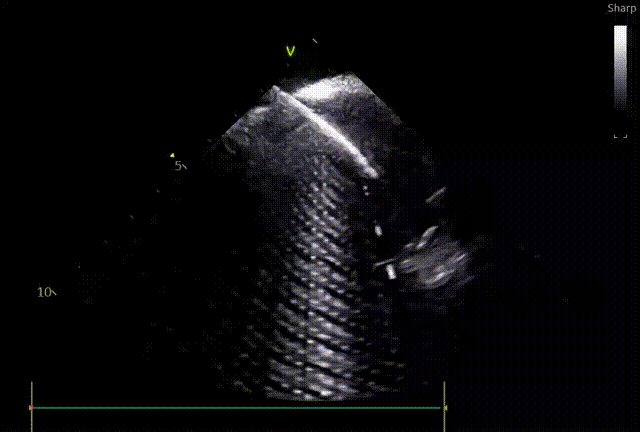

“超声下监测放电过程中,没有看到任何气泡产生。”

不仅中国专家反馈很好,同时FARAPULSE的安全性更是得到数据的验证,超过1.7万例真实性世界研究MANIFEST-17K中,食道瘘,肺静脉狭窄,永久性膈神经损伤均为0%1。手术过程中临床医生以往需要担心的问题得到解决,手术过程更加安心,也为患者带来更加安全的手术体验。

脉冲消融技术的“组织选择性”原理,避免对心肌毗邻组织的损伤